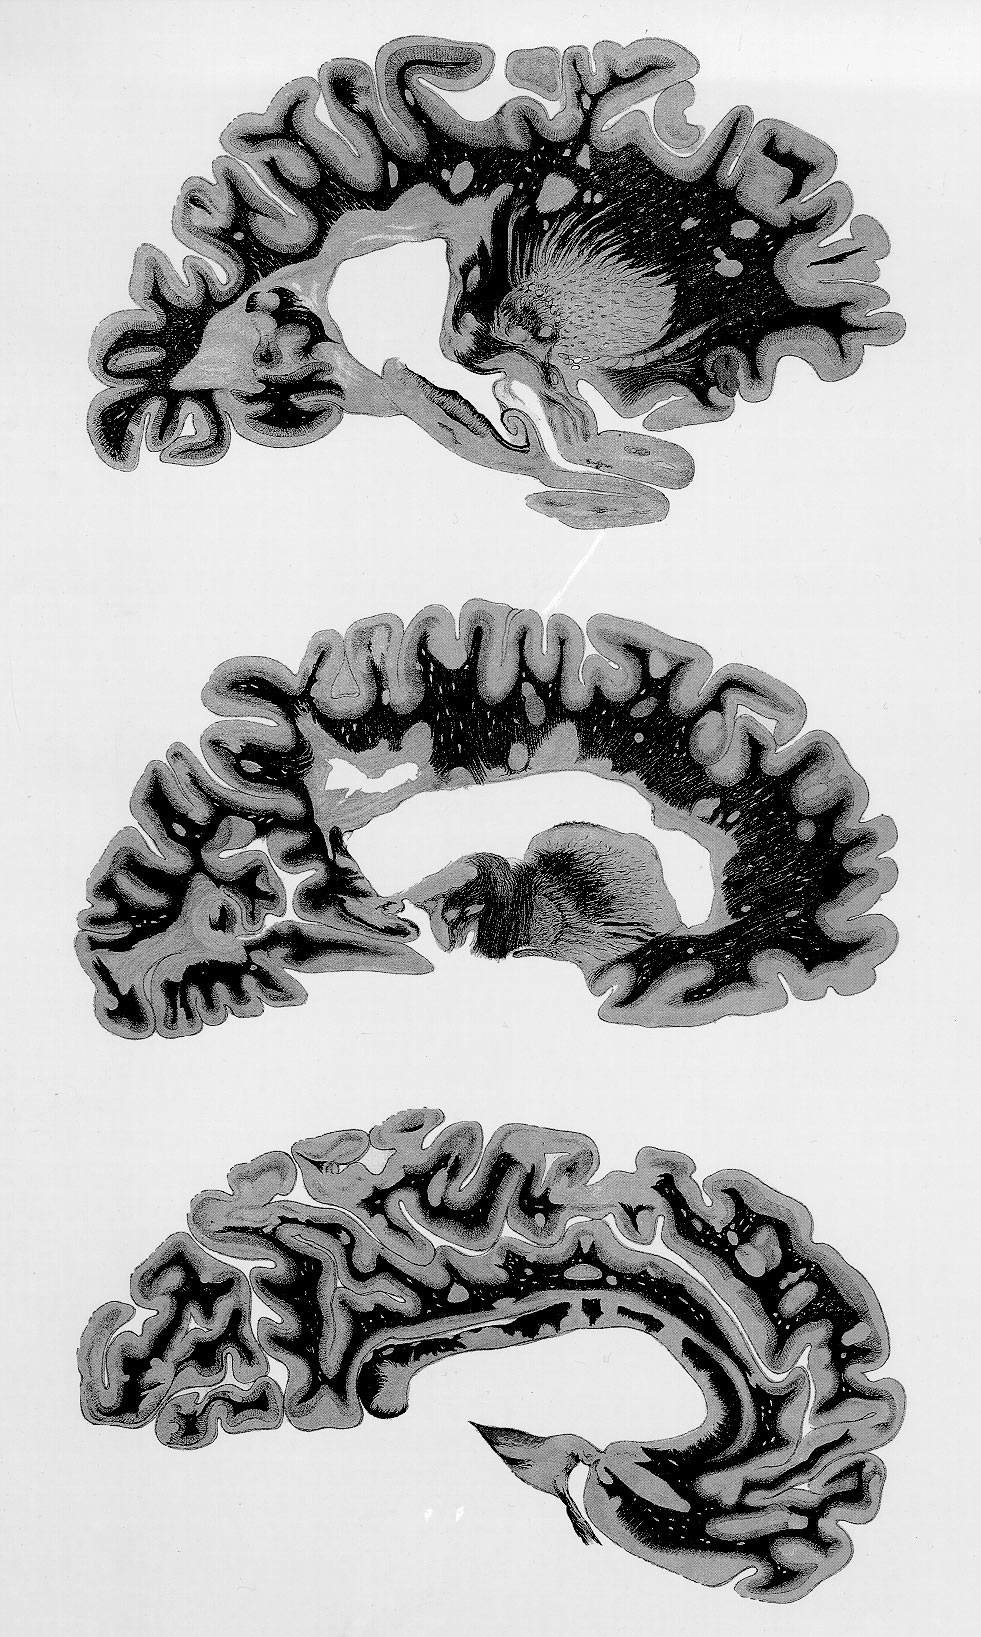

Plate VI.

In addition to a projection of a number of compact and many finely dentate, basally connected lesions off of the ventricular border, the cerebral hemisphere's three slices parallel to the median plane display a gradual lesion detachment and eventual free scattering outwards of the first involved zone into the entire cerebrum.

The cerebral hemisphere's paramedian sections show "extensive plaques, strongly involving, even penetrating the corpus callosum" (lower figure); "many others affect both cerebral white matter and cortex; the most strongly sclerosed, i.e. scarred, areas are in the ventricle walls" .

Otherwise, the account on the fourth case of Siemerling and Raecke's 1914 report merely mentioned that also spinal cord, brain stem, cerebellum, and optical nerves had at all levels been comparably involved.

In this plate, the ventricle-based lesion picture appears as a sort of intermediate between the damages projected off of the ventricular border, shown in Plate V, fig. A, and the vast epiventricular lesion depicted in Plate IV, fig. 1. Illustrated for the first time here is that specific cerebral plaques may also emerge, apparently independently, peripheral to the ventricle-based lesions. Besides, it is once more shown that the grey matter, though poor in myelin, is not spared.